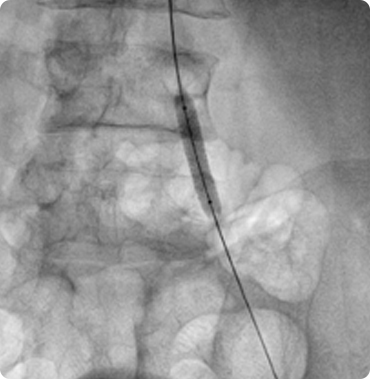

Interesting Cases